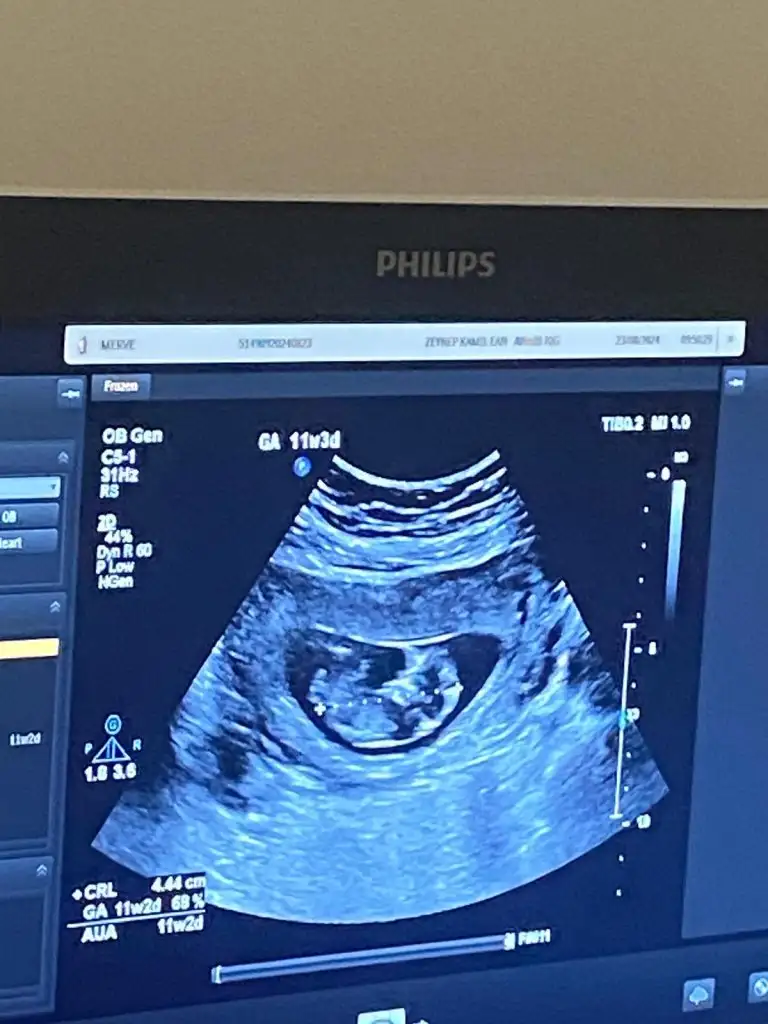

Kızlar 14+3 cinsiyet tahmini alabilir miyim sizden ricam tesekkur ederim 🙏